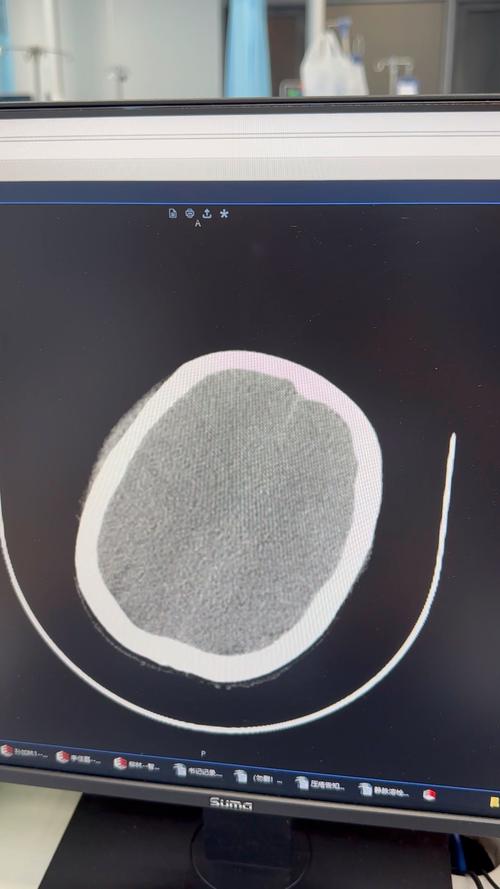

- 头颅CT:如果出血量大,或者宝宝出现明显症状,需要更精确地评估,医生可能会建议做CT检查,CT能更清晰地显示出血的范围和量,但有辐射,通常不作为首选筛查工具。

(图片来源网络,侵删)- 安静的环境:减少不必要的刺激,让宝宝充分休息。